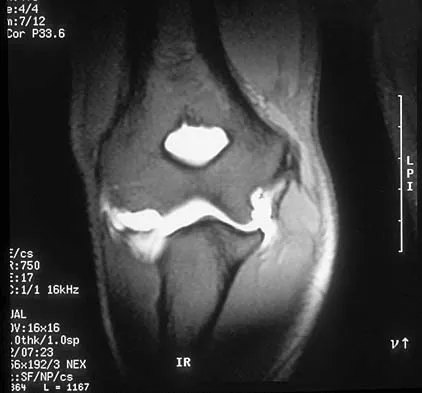

Question 548High Yield

A 78-year-old patient undergoing revision total knee arthroplasty has bone loss throughout the knee at the time of revision. A distal femoral augment is used to restore the joint line. One month after surgery, the patient reports pain and is unable to ambulate. A lateral radiograph is shown in Figure 34. What is the most likely etiology of this problem?

Explanation

Instability is a leading cause of failure following total knee arthroplasty. Instability can present as global instability, extension gap (varus/valgus) instability, or flexion gap (anterior/posterior) instability. Treatment options are numerous based on the exact pathology. The radiograph reveals anterior/posterior instability with dislocation consistent with flexion gap instability. A loose flexion gap can allow the femoral component to ride above the tibial cam post mechanism, resulting in dislocation. Distal femoral augments treat extension gap instability, whereas tibial augments can treat both flexion and extension gap instability. Posterior condyle augments at the distal femur can also be used to treat flexion gap instability. Flexion gap instability is further aggravated by extension mechanism incompetence. Note the excessively thin patella on the lateral radiograph. Pagnano MW, Hanssen AD, Lewallen DG, et al: Flexion instability after primary cruciate retaining total knee arthroplasty. Clin Orthop 1998;356:39-46. McAuley J, Engh GA, Ammeen DJ: Treatment of the unstable total knee arthroplasty. Inst Course Lect 2004;53:237-241.